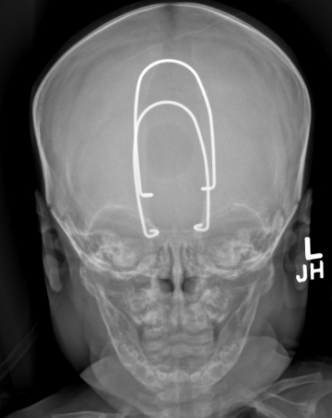

Nguyen decided to think out of the box, contemplating how surgeons could perform such a procedure more effectively. He decided to incorporate cranial springs into his concept.

"Cranial springs are also not new. They've been around for a good 25 years as well. Basically, the concept is, you have a titanium spring or a steel spring, and then you bend it into a shape that has a certain force. It just pushes things out," Nguyen said. "It's been pretty prominent in a lot of centers, mostly in Europe, but more adopted now in the US over the last decade or so. It's a tool like anything else. However, it really hasn't been used for this application. We thought about this long and hard, like, well, maybe this is an opportunity to try some of this technology that we've been using for other aspects."

The cranial springs must be watched closely once they are put into a child's skull because they work quickly, according to Nguyen. Once doctors have achieved their goal, the springs are removed in a small outpatient surgery.

"In some cases, that's all you need. You're done. No helmet," Nguyen said. "In some cases, where the child, in particular, is a little bit younger and the skull is still molding, then we put a helmet on just for fine-tuning. And so you go from 12 months [of wearing the helmet] down to just a few months."